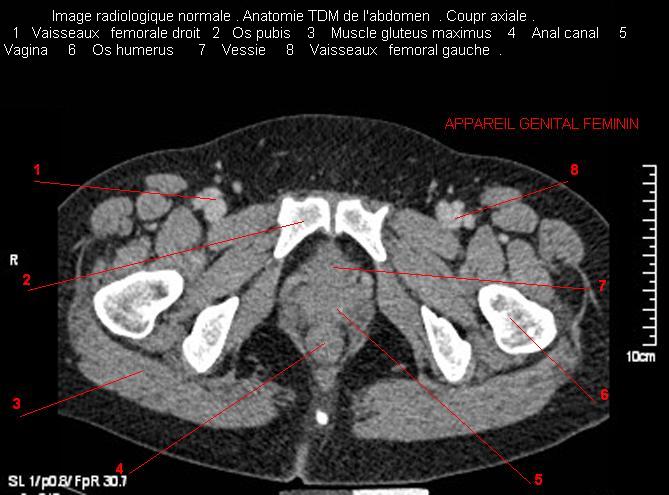

Images radiologique TDM normale de l'abdomen et tube digestif en coupe axiale ( CT scanner )  :

Coupe axiale     Coupe frontale      Coupe  sagitale